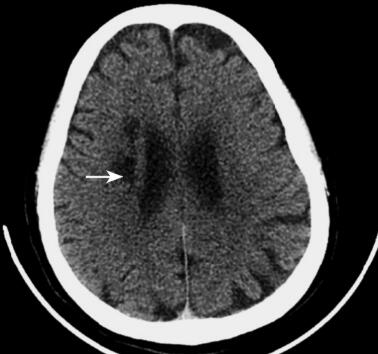

头颅、颈部螺旋计算机断层增强扫描及血管扫描(2011年11月3日):轻度脑萎缩,右侧放射冠脑梗死灶(图3),脑动脉硬化,未见颅内外血管狭窄。

图3 CT结果:右侧放射冠低密度脑梗死灶(箭头)